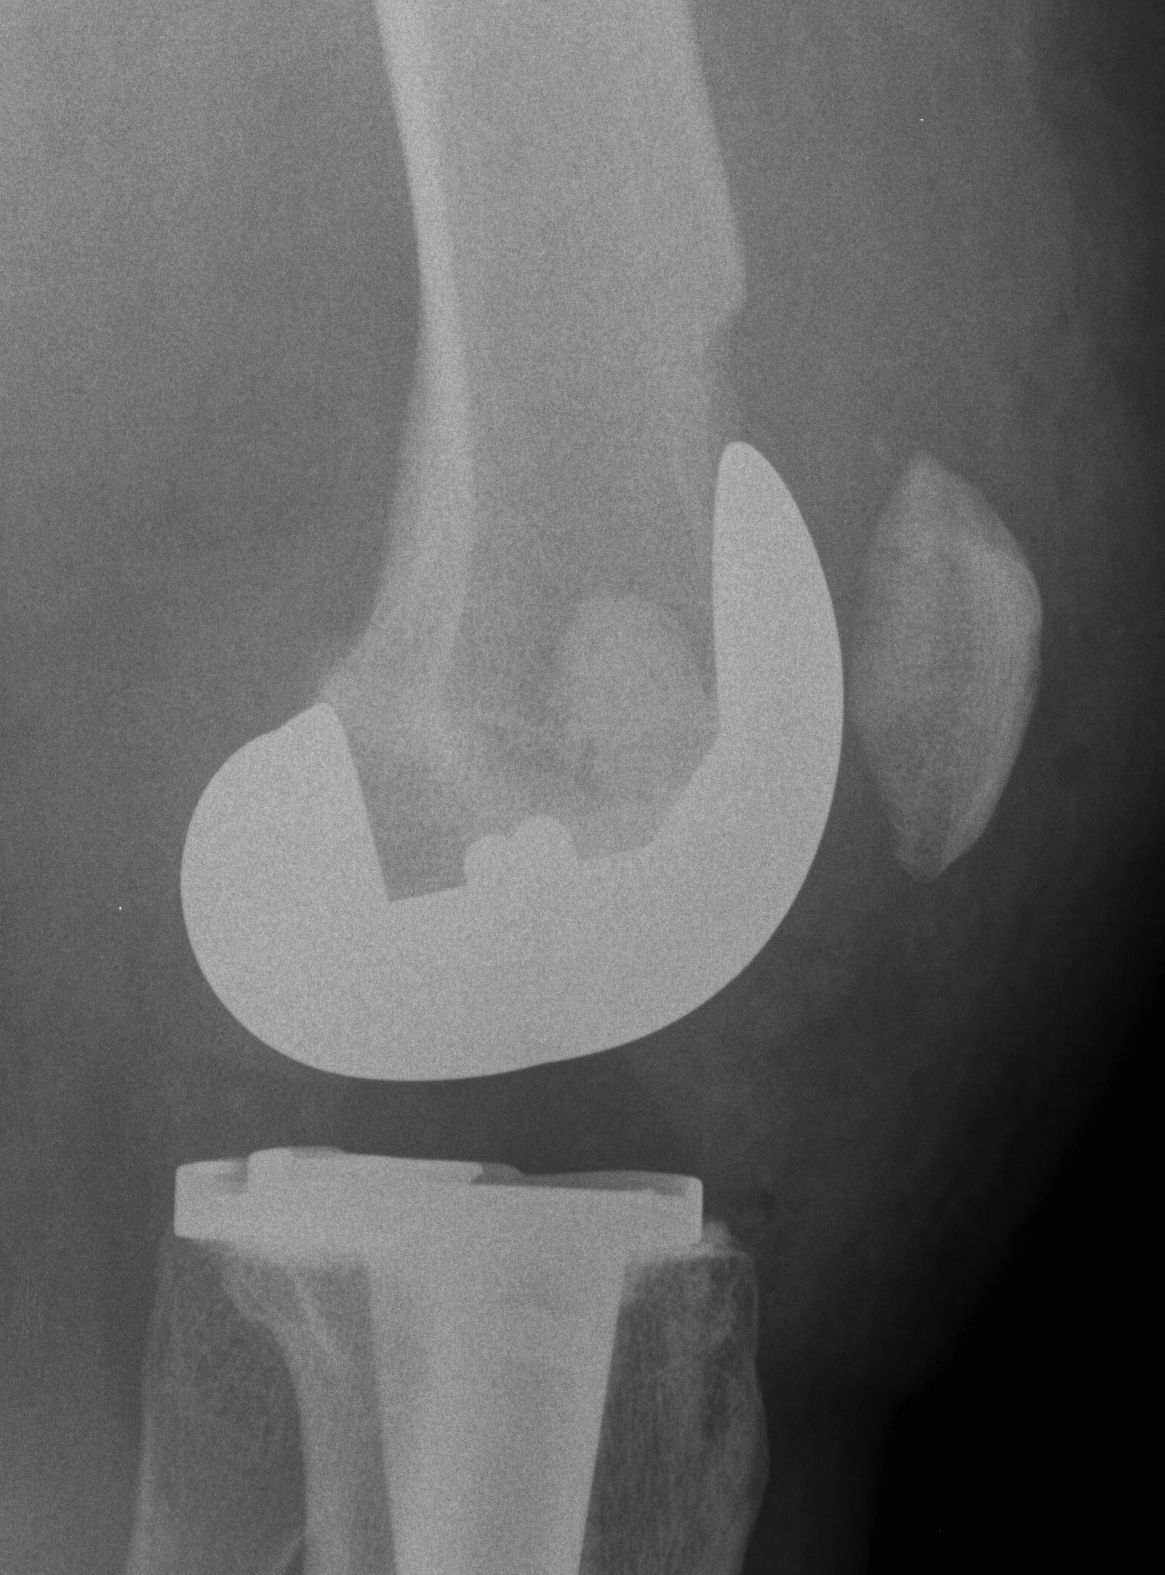

TKR Intraoperative condylar fractureTKR Condylar Fracture Lateral